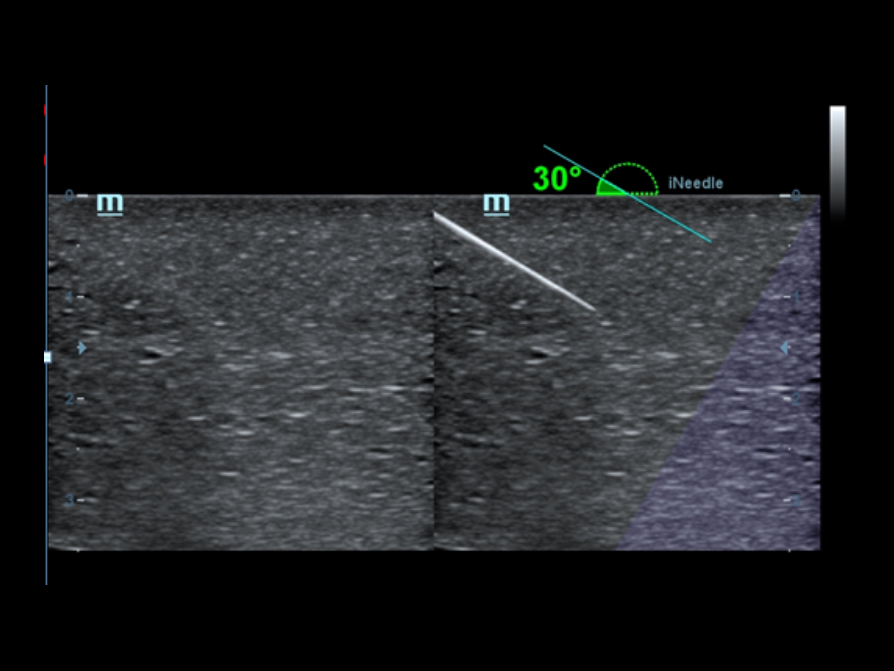

iNeedle?

Doskona?e narz?dzie do wykonania biopsji: pozwala na dopasowanie k?ta linii skanowania w celu uzyskania lepszej widoczno?ci ig?y, nerwów i drobnych naczyń krwiono?nych.